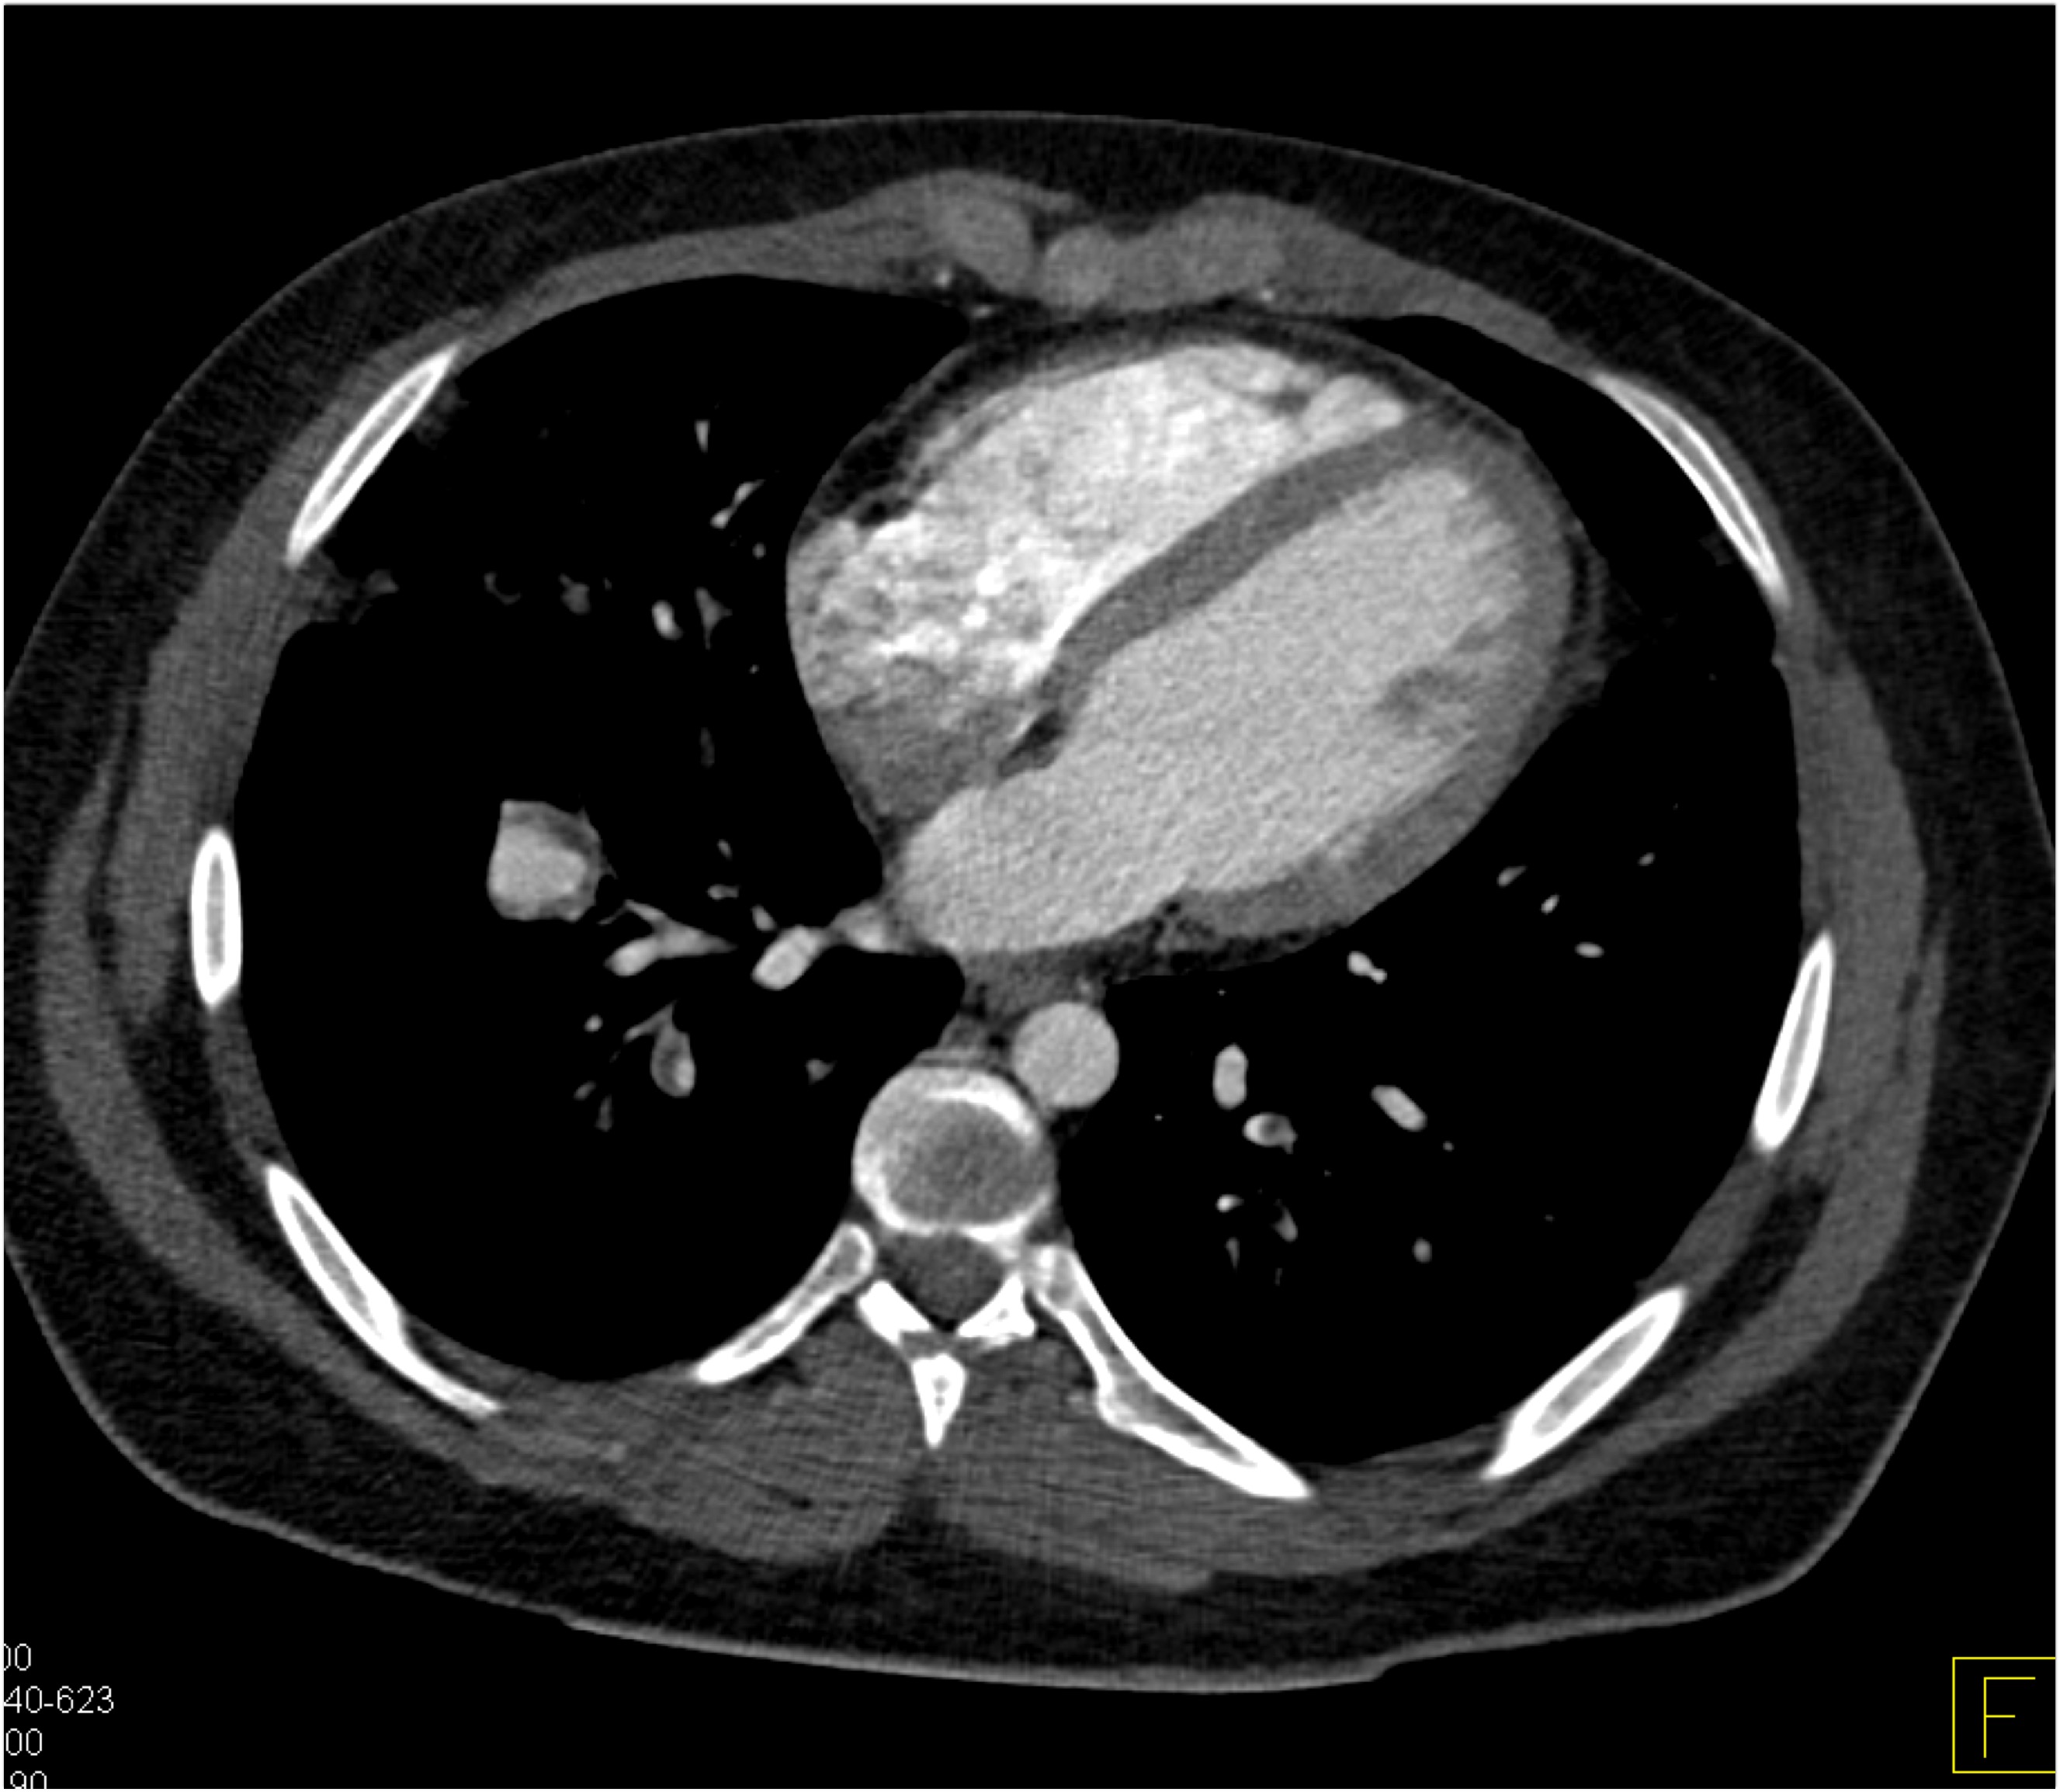

4) The mass in the right lower lung in this patient post trauma is

pulmonary contusion

lung infarct

adenocarcinoma

pulmonary laceration